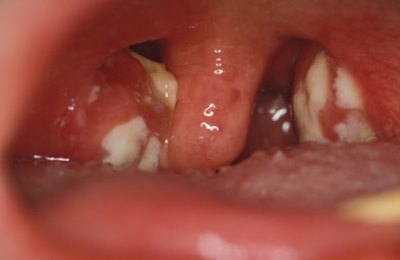

Белый налет и гнойники на миндалинах при отсутствии повышенной температуры у взрослого или ребенка может говорить о двух заболеваниях: ангине или дифтерии.

Фибринозный тонзиллит наиболее ярко выражается появлением белого налета на миндалинах, и поэтому его можно перепутать с дифтерией при отсутствии грамотной диагностики. Также появляются гнойники, содержащие гной, прямо в горле.

Налет в горле – это главный признак воспалительного процесса на гландах (также, вполне вероятно, в горле собрался гной). Его наличие говорит о патологии миндалин, которое вскоре может привести к более опасным заболеваниям, например, поражению сердца после тяжело перенесенной ангины.

К тому же налет говорит, скорее всего, о гнойном процессе. В мокроте выделяется гной, в горле могут вскрываться гнойники.

Белые точки и пятна на миндалинах – прямой симптом серьезной патологии, лечить которую, видимо, придется довольно долго. Сниженный иммунитет – первоначальная причина того, что появляются подобные патологии, которые сопровождает налет на гландах, гнойники и гной в мокроте.